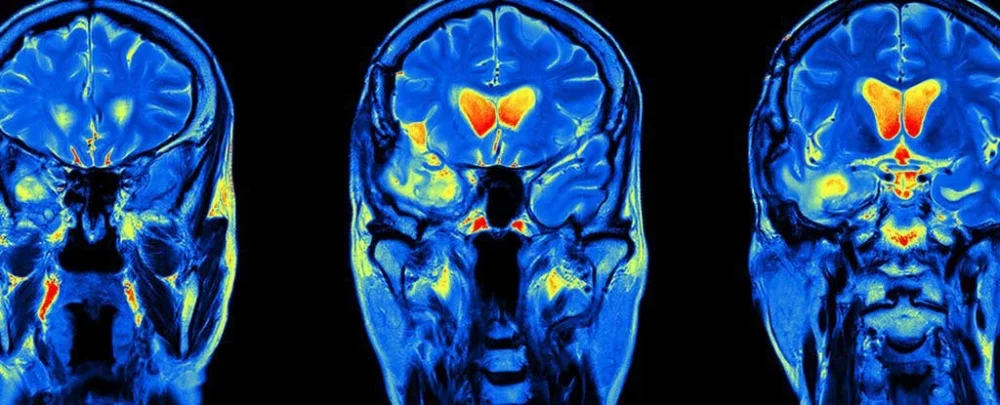

Thuốc trị sốt rét có thể chữa ung thư não

Xuất hiện tia hy vọng mới trong lĩnh vực chữa trị bệnh ung thư não khi các nhà khoa học vô tình nhận ra được hiệu quả bất ngờ trong việc hỗ trợ tiêu diệt khối u của một loại thuốc chuyên dùng để điều trị… sốt rét.